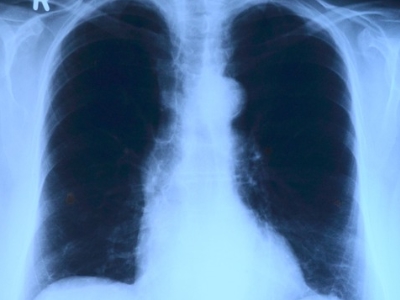

폐와 흉막에 문제가 생겨서 가슴이 뻐근하고 아플 수 있습니다. 의심되는 증상이 있다면 검사받아보는 것이 필요합니다.

폐렴

세균이나 바이러스, 곰팡이 등에 의해 폐에 염증이 생긴 것을 말합니다. 면역력이 떨어졌을 때 발병하기 쉬운 질환이며 증상은 초기에는 감기와 비슷합니다. 고열, 기침, 가슴 통증, 짙은 가래 색깔, 호흡곤란 등이 있다면 검사받아봅니다.